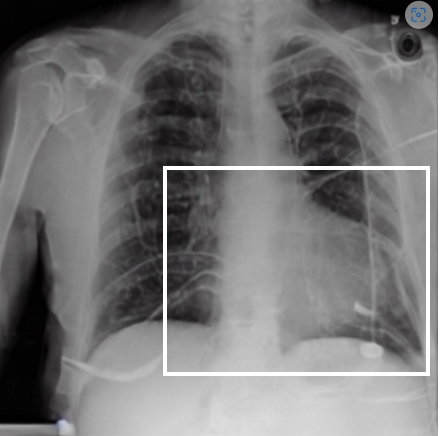

4.1 Qualitative Evaluation of Healthy Counterpart Generation

Example images from the disease COVID-19 Radiography Database and their generative healthy counterparts are given in figure 2. The images on the far left are instances of the lung opacity class from the real images in the dataset. The images in the middle column are examples of the generated healthy counterfactuals obtained via latent space diffusion, with RadBERT-guided textual-conditioning via a conditional prompt “normal chest x-ray”. A total of 75 diffusion inference steps are used with image conditioning strength=0.85 and guidance scale=7.5. (The former indicates the level of constraint on changes to the original input image and the latter is the weight given to the textual encoder conditioning in the generation of the image, ranging over [0,1] and [0,9], respectively).

Side-by-side inspection of the generated healthy counterfactuals (as per fig. 2) suggests that, as required, only minimal perturbation is made to the original image with respect to healthy pixels -i.e. localized image sites without structural medical defects. (In the top row, the medical structural defect in the original image is due to a lung opacity, and characterized via a relatively complex interaction between the imaging modality and subject manifesting as ‘gaps’ in the corresponding portions of the lung scan). The healthy/non-healthy discrepancy maps in all of these cases are obtained via masked subtraction of the original image from the generated image (the ground truth segmentation masks correspond to the broad area of interest –i.e. the complete lung). The generated healthy tissue is thus a subset of the mask and is shown in the final column of fig. 2 for the respective cases.

In the context of a VANT-GAN[20]-based approach, this highlighted material constitutes the diagnostic counterfactual visual attribution, i.e. the selection of material relevant to the diagnosis of the unhealthy condition. Healthy counterfactual generation was performed for the complete datasets in the three unhealthy classes, i.e Lung opacity, Viral Pneumonia and COVID, examples of which are given in fig. 3 for the three classes (all of the generated healthy counterfactuals from this experiment can be found on https://huggingface.co/ammaradeel/diffusionVA). Visual inspection indicates that the generated counterfactuals are, in general, visually plausible with minimal perturbation made to the unhealthy image overall. Moreover, the healthy counterpart generation does not appear to unnecessarily affect aspects of the images unrelated to the medical condition, the model selectively making changes to the unhealthy regions in a structurally plausible manner, e.g. generating missing portions of the lung without generating extraneous lung material where it would be expected to normally exist (e.g. in the abdominal cavity).